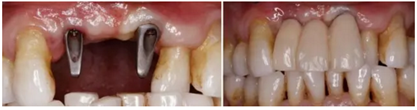

(4)3-shape數(shù)字化口掃進(jìn)行數(shù)據(jù)采集及最終修復(fù)體制作

(5)個(gè)性化基臺(tái)及臨時(shí)修復(fù)體戴入,軟組織成形

(6)最終修復(fù)體戴入

數(shù)字化口腔掃描以其高效、快捷、精確、簡(jiǎn)便、舒適性高等特點(diǎn)逐漸代替?zhèn)鹘y(tǒng)印模方式,數(shù)字印模無(wú)明顯盲區(qū)、三維形態(tài)精確、可靠性高,便于醫(yī)技遠(yuǎn)程交流,制定最佳方案,減少了修復(fù)體返廠的風(fēng)險(xiǎn)。數(shù)字印模的精確性也為最終修復(fù)體的長(zhǎng)期密合性和穩(wěn)定性提供了保障。